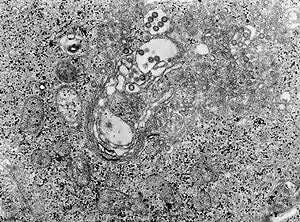

Arbovirus infection

Tissue infected with the Rift Valley fever virus